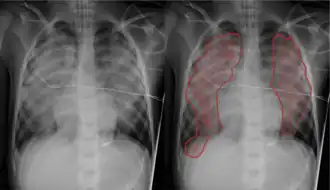

| Pulmonary edema with small pleural effusions on both sides | |

Chest X-ray has been used for many years to diagnose pulmonary edema due to its wide availability and relatively cheap cost.[4] A chest X-ray will show fluid in the alveolar walls, Kerley B lines, increased vascular shadowing in a classical batwing peri-hilum pattern, upper lobe diversion (biased blood flow to the superior parts instead of inferior parts of the lung), and possibly pleural effusions. In contrast, patchy alveolar infiltrates are more typically associated with noncardiogenic edema.[3]